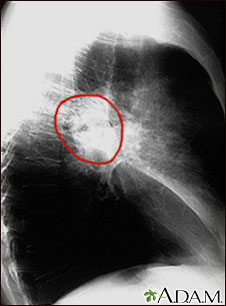

A lateral view of a CXR in a patient with central cancer of the lung.